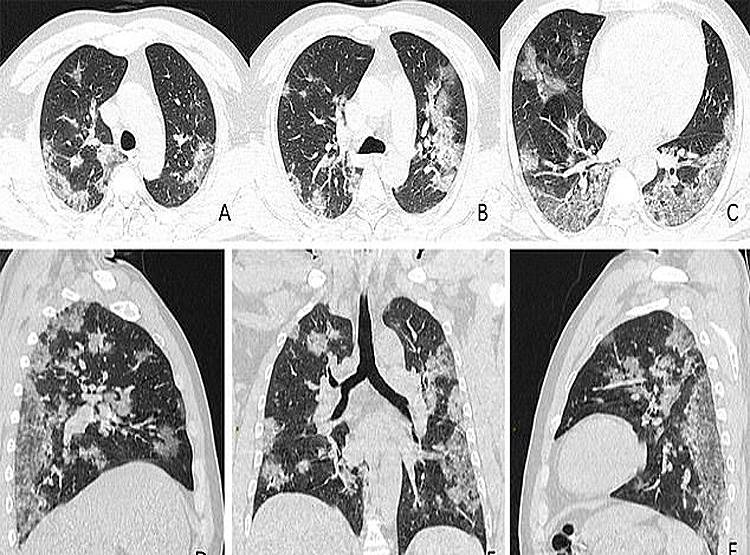

दुनियाभर के डॉक्टरों को कोरोना वायरस मरीजों के एक्स-रे और सीटी स्कैन में ऐसे ही सफेद चकत्ते देखने को मिल रहे हैं. ये सार्स और मर्स जैसी बीमारियों के एक्स-रे से मिलते-जुलते हैं. डॉक्टरों का कहना है कि कोरोना वायरस का एक्स-रे सार्स और मर्स के एक्स-रे की तुलना में ज्यादा भयावह हैं. रेडियोलॉजिस्ट को कोरोना के सभी मरीजों के एक्स-रे और सीटी स्कैन में ग्लास ओपेसिटी ज्यादा देखने को मिल रही है. (फोटोः RSNA)

ये तस्वीरें रेडियोलॉजिकल सोसाइटी ऑफ नॉर्थ अमेरिका (RSNA) द्वारा जारी की गई हैं. सोसाइटी ने करीब 1000 मरीजों की जांच की है. सभी की छाती का एक्स-रे और सीटी स्कैन किया गया है. इसके बाद सभी के एक्स-रे और सीटी स्कैन में समानता खोजी गई. तब जाकर पता चला कि आखिर कोरोना मरीज के फेफड़ों में सफेद चकत्ते कितने भयावह हैं. (फोटोः RSNA)

वुहान की ही एक 54 वर्षीय महिला के फेफड़ों का सीटी स्कैन किया गया. इसमें भी ग्लास ओपेसिटी पाई गई. इस महिला को कोविड-19 की वजह से भयानक स्तर का निमोनिया हो गया था. इस महिला को सांस लेने में इतनी ज्यादा दिक्कत हो रही थी कि उसे ऑक्सीजन देना पड़ रहा था. (फोटोः RSNA)